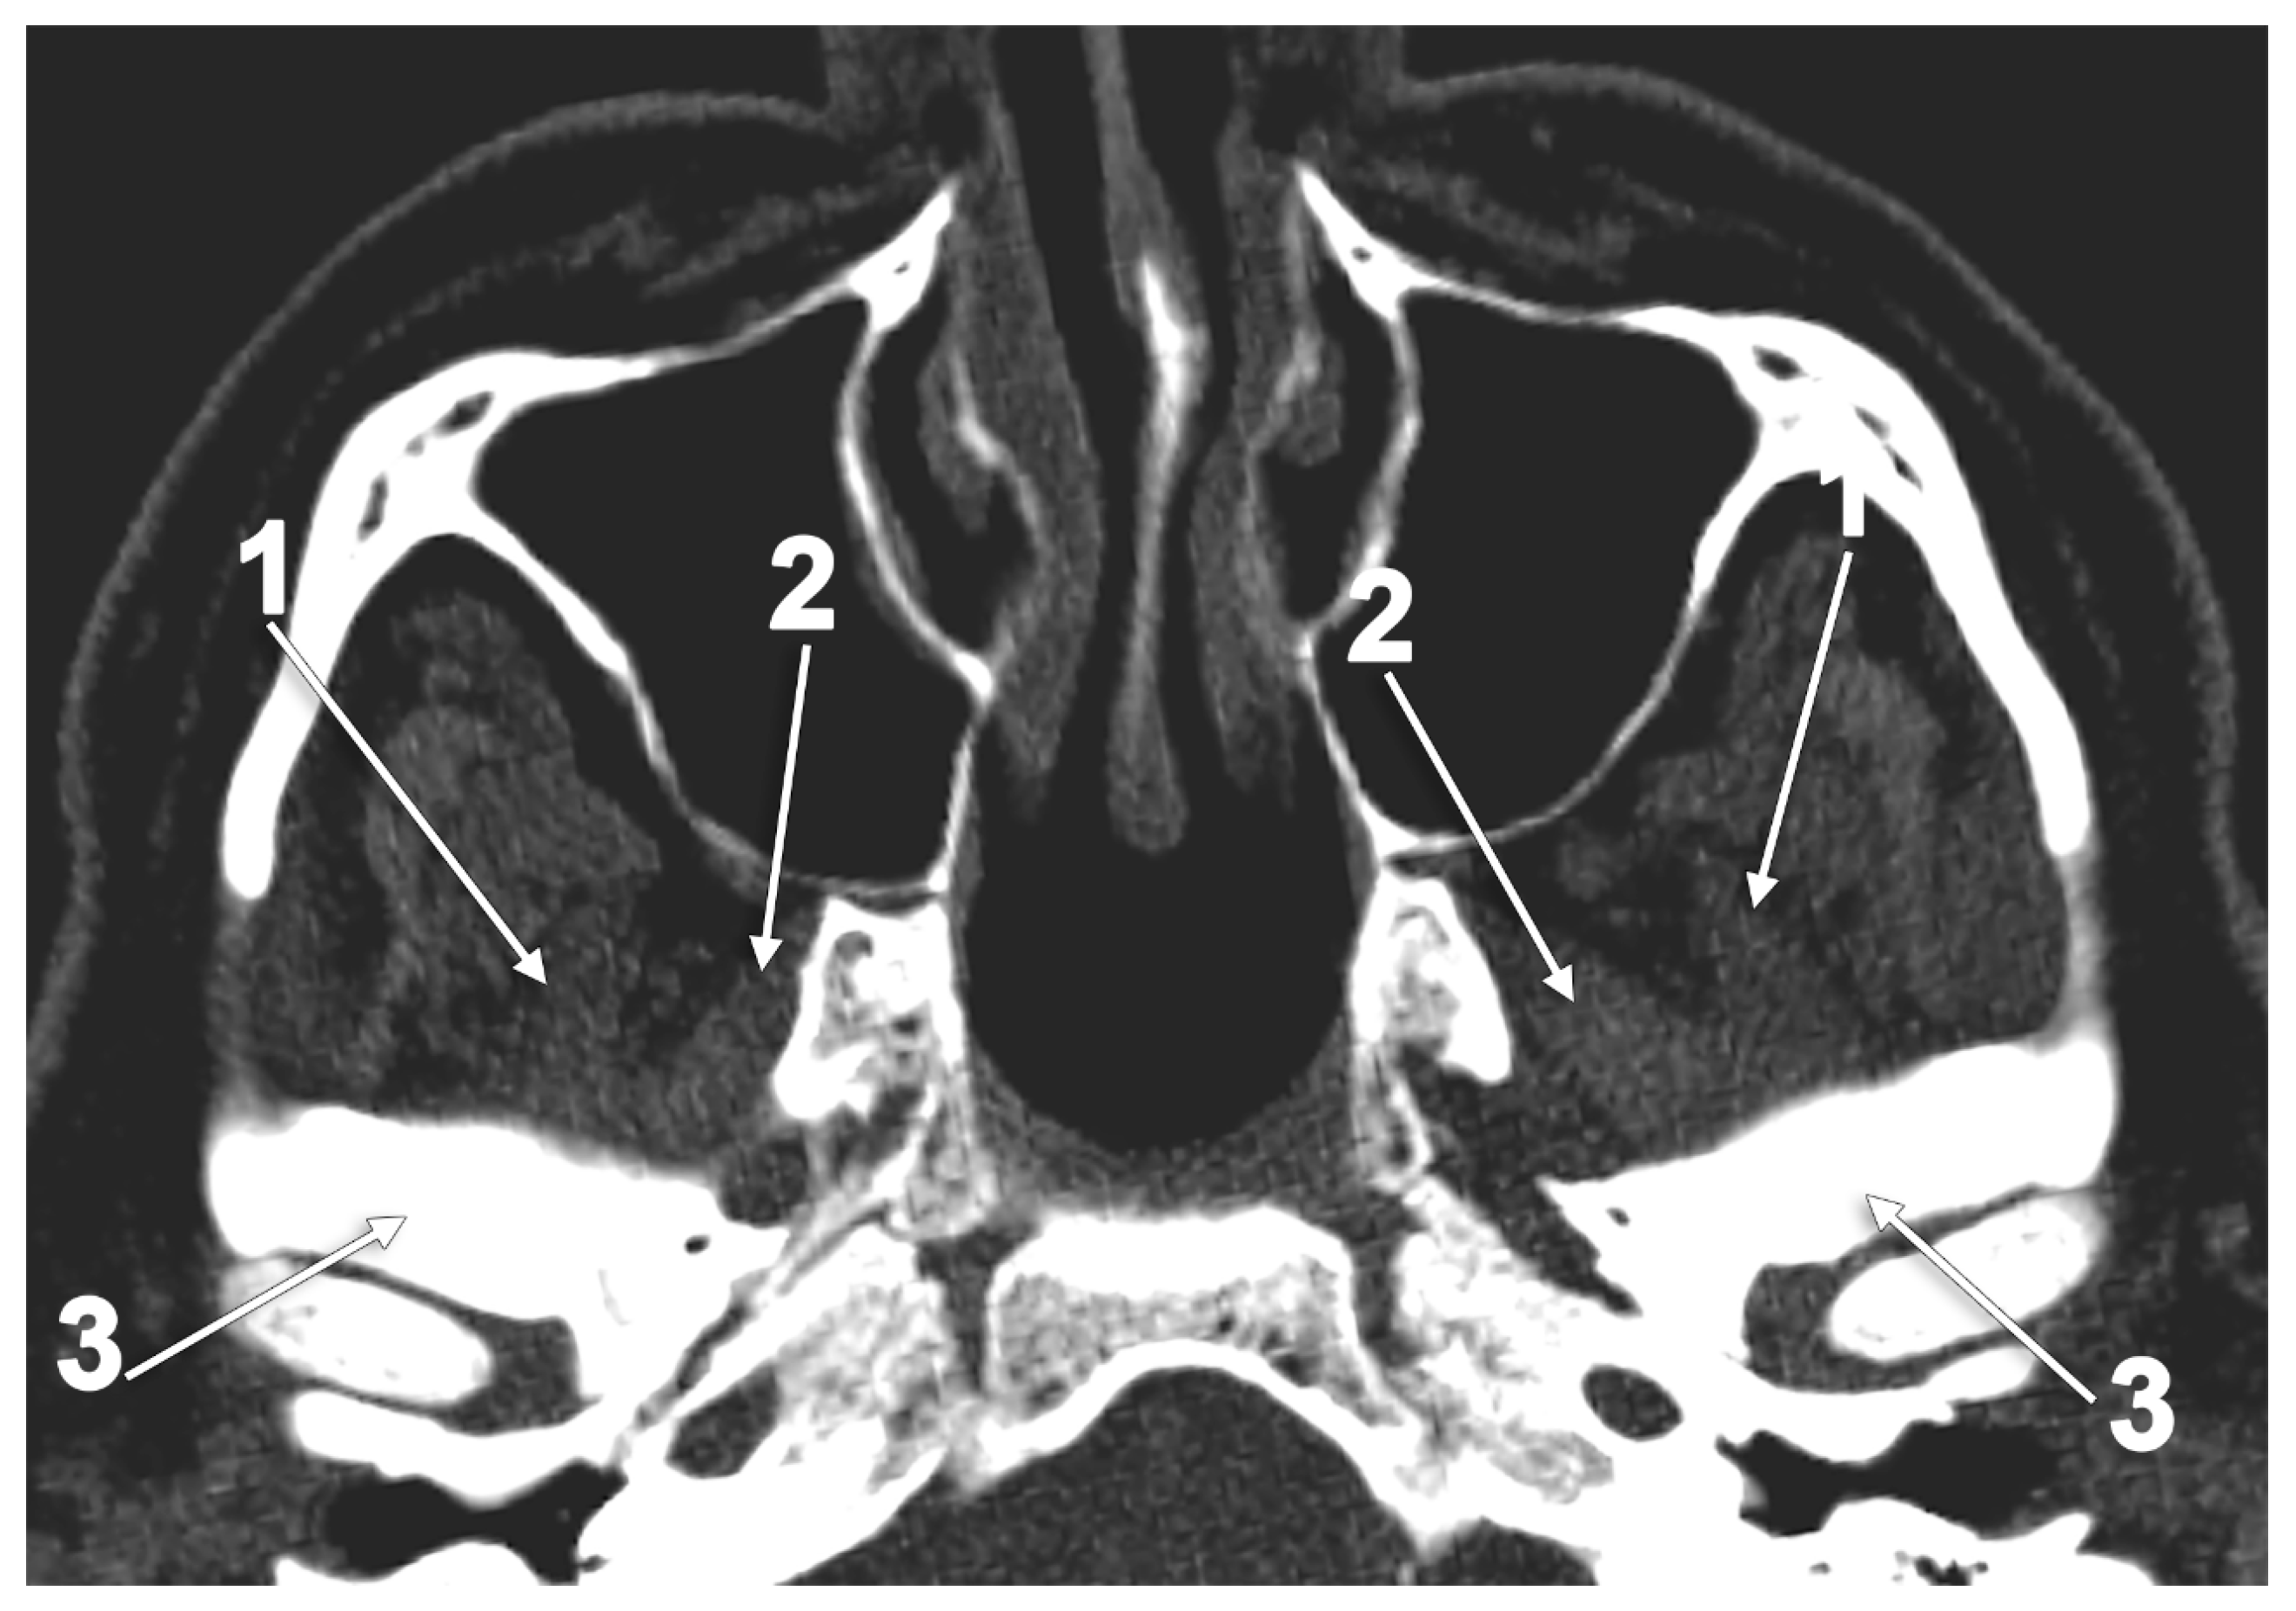

- Birou, G.; Garcier, J.M.; Guillot, M.; Vanneuville, G.; Chazal, J. A study of the lateral pterygoid muscle: Anatomic sections and CT appearances. Surg. Radiol. Anat. 1991, 13, 307–311. [Google Scholar] [CrossRef] [PubMed]

- Antonopoulou, M.; Piagou, M.; Anagnostopoulou, S. An anatomical study of the pterygospinous and pterygoalar bars and foramina—their clinical relevance. J. Craniomaxillofac. Surg. 2008, 36, 104–108. [Google Scholar] [CrossRef]

- Henry, B.M.; Pekala, P.A.; Fraczek, P.A.; Pekala, J.R.; Natsis, K.; Piagkou, M.; Tomaszewski, K.A.; Tomaszewska, I.M. Prevalence, morphology, and morphometry of the pterygospinous bar: A meta-analysis. Surg. Radiol. Anat. 2020, 42, 497–507. [Google Scholar] [CrossRef]